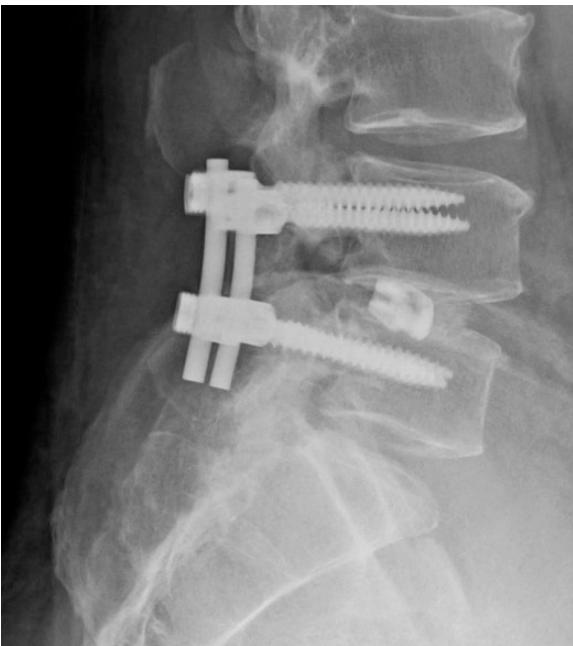

Degenerative Spondylolisthesis

- Definition: Common degenerative condition characterized by subluxation of one vertebral body anterior to the adjacent inferior vertebral body with intact pars

- Demographics: Most common in females over 40 years of age, at the L4-5 level

- Diagnosis: Lateral radiographs; flexion and extension lateral lumbar radiographs can identify degree of instability

- MRI: Helpful for central or foraminal stenosis

Treatment:

- Nonoperative: Trial with NSAIDs and physical therapy

- Surgical: Indicated for progressive disabling pain that has failed nonoperative management, and/or progressive neurological deficits